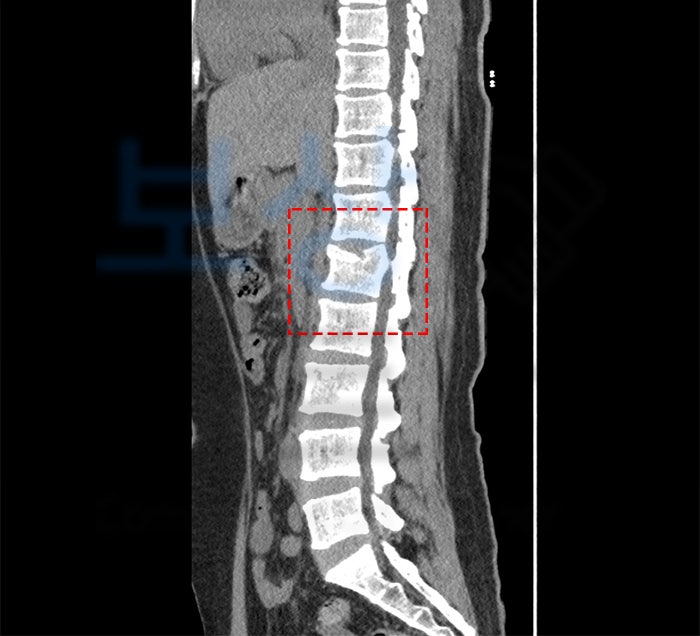

엑스레이 사진을 보면 허리 부근의 척추뼈 하나가 찌그러진 것을 볼 수 있습니다. 이러한 척추체 골절을 **'압박골절' **이라고 하는데요. 하중을 가장 많이 받는 흉추 11,12번이나 요추 1,2,3번 뼈가 가장 흔하게 압박골절됩니다.

혹시라도 척수 침범의 여부가 있는지 확인해야 하므로 CT나 MRI 등의 정밀 검사가 필수로 진행됩니다. 환자분께서는 나이가 젊으셔서 **'보존적 치료'**를 시행하였는데요. 이것은 수술을 하지 않고 보조기만 착용한 상태로 골유합(뼈가 붙는것)을 기다리는 것입니다.

특히나 요추 1번 압박골절의 경우에는 척추의 압박률이나 변형 각도에 따라서 장해 지급률(%) 평가가 달라질 수도 있는데요. 그러므로 이러한 후유장해 보험금을 제대로 보상받으려면 전문가 선임이 필수라고 할 수 있습니다.

요추 1번 압박률 20%

흉추 12번 - 요추 2번간 후만각 17도

외상 관여도 100%, 7년 한시장해